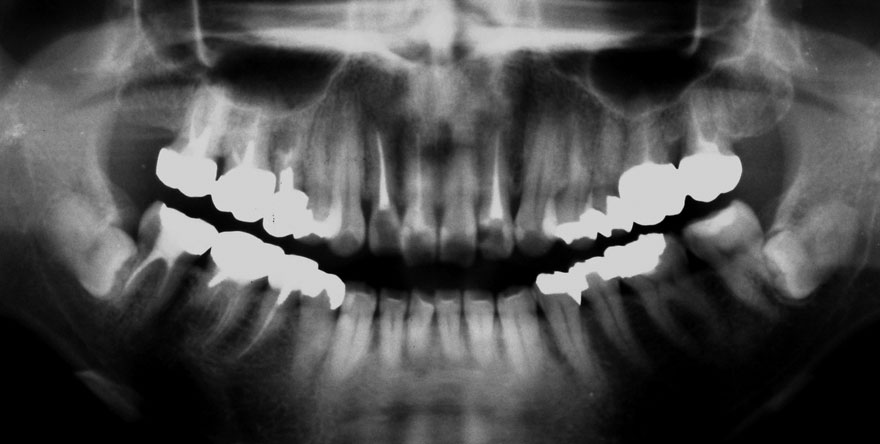

初診時 25歳 男性 平均歯槽骨喪失量:1.43mm

河田歯科医院

30年後 55歳

平均歯槽骨喪失量:1.56mm

22年間喪失量:-0.14mm

年間喪失速度:-0.005mm

(ケア頻度:4.21ヵ月ごと)